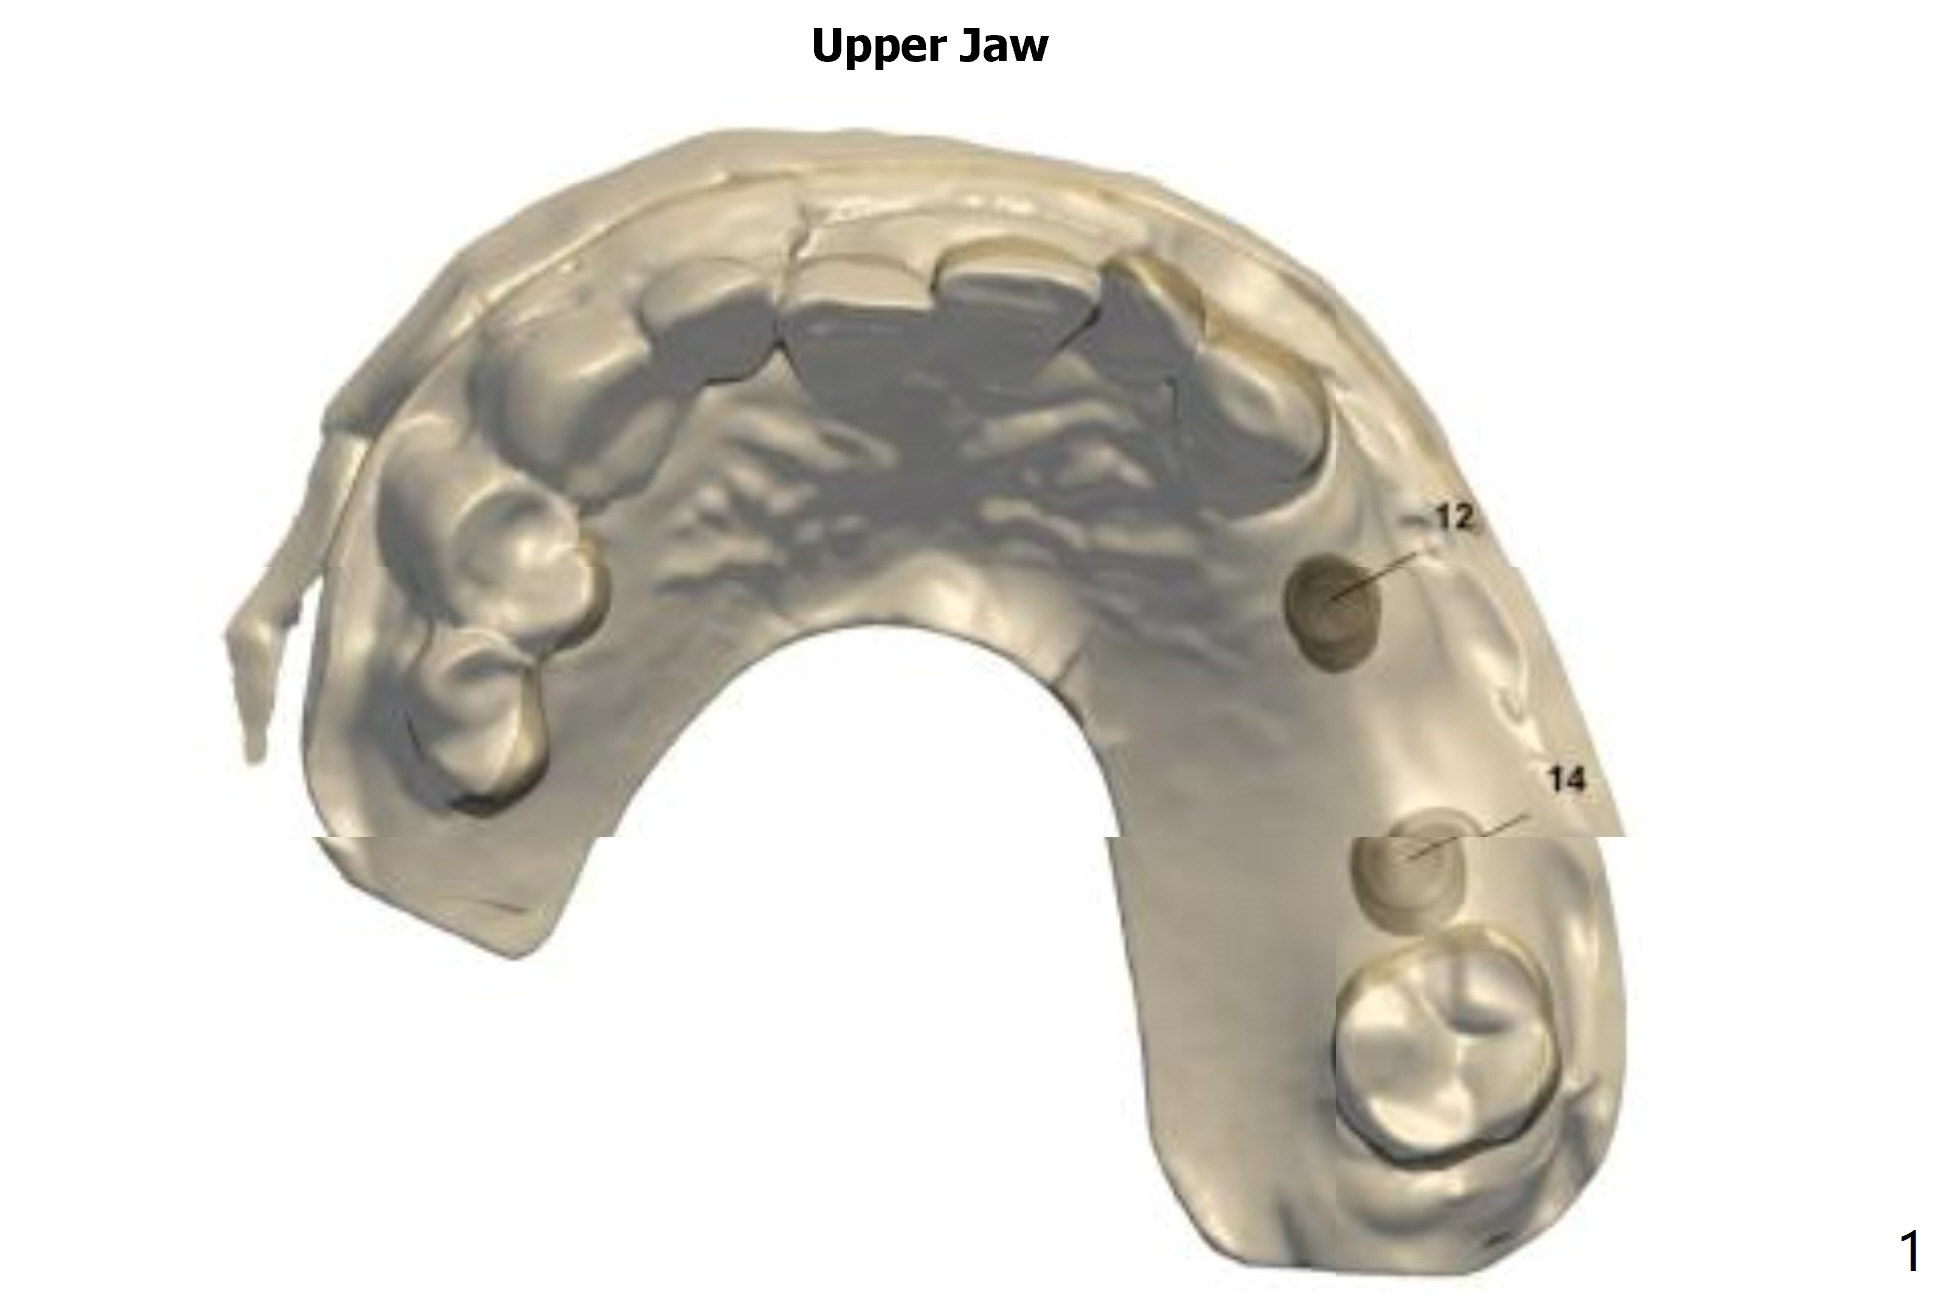

1st Guided Bridge

Return to Upper Molar Immediate Implant, Armaments